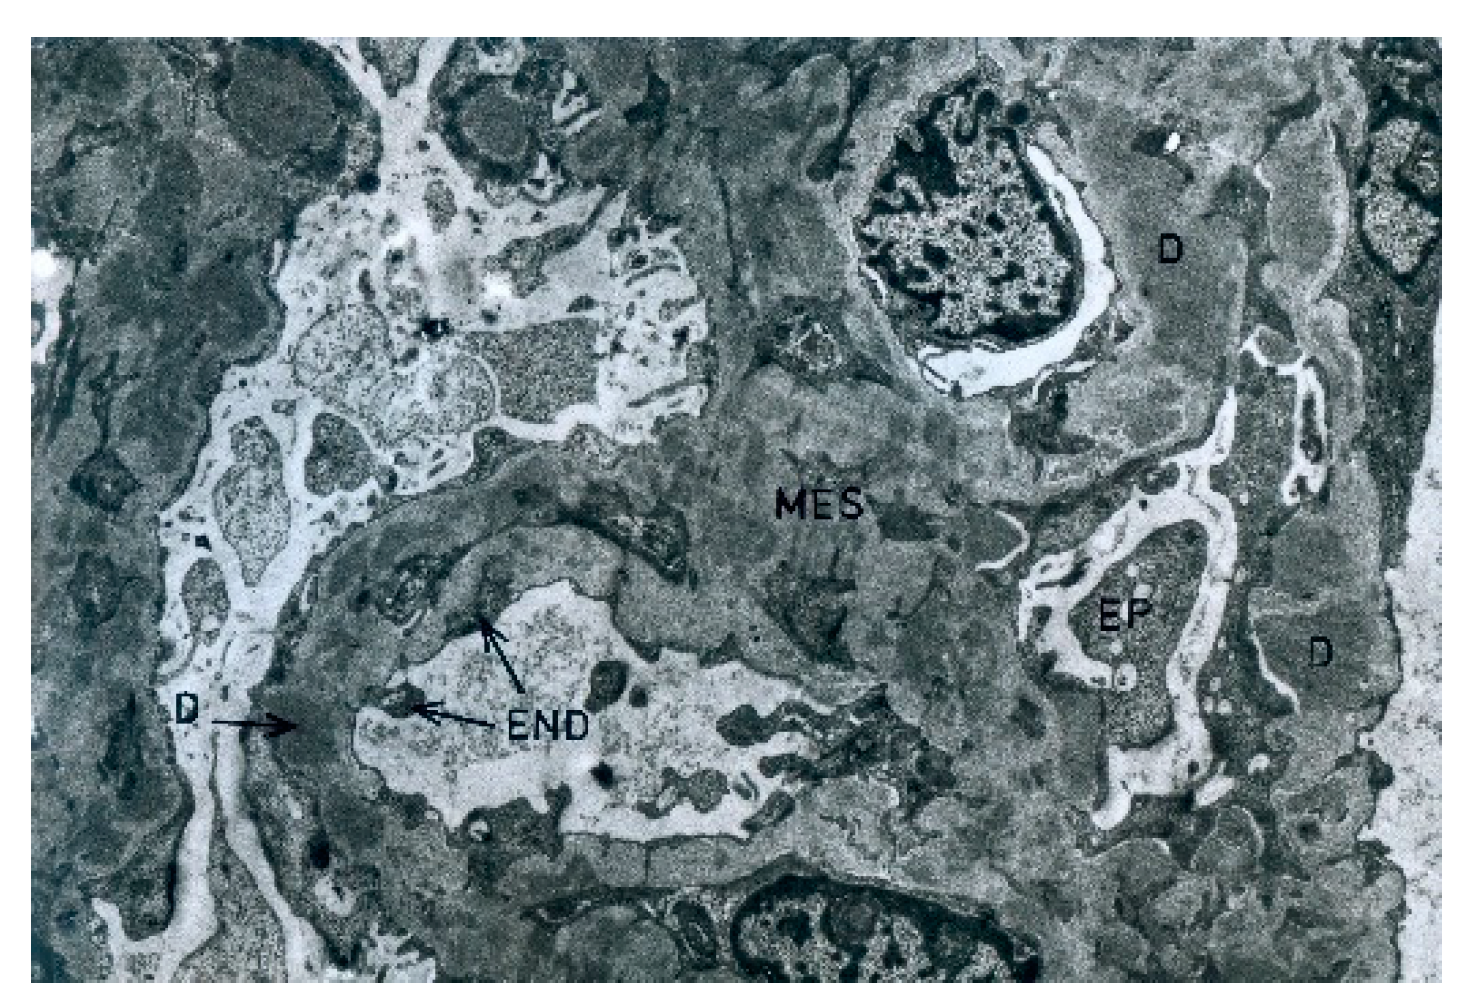

During the electron microscopic examination, the transposition of mesangial cell protuberances to the periphery of the capillary loops, as well as the presence of a ‘double’ basement membrane resulting from the presence of subendothelial deposits, were visible in the glomeruli (Figure 6). Glomeruli, with transposition of mesangial cell protuberances to the periphery of the loop, as well as in the presence of subepithelial deposits, were also noted (Figure 7).

Figure 7. The case of C3GN. Electron microscopic image of the glomerulus with transposition of mesangial cell protrusions to the periphery of the capillary loop and presence of subepithelial deposits. Electron microscopy, 8750× magnification. Mes, mesangium; EP, epithelium; END, endothelium; D, deposits.